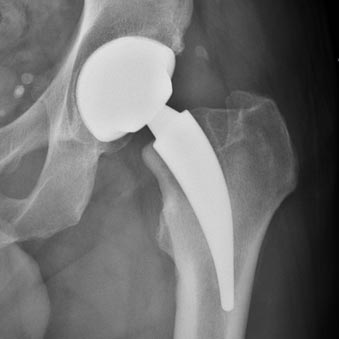

Total Hip Arthroplasty via Bikini

The prosthesis is placed through a 6 to 10 cm incision made on the anterior surface of the hip, following the groin crease (bikini line). This treatment is indicated in degenerative joint disease, post-traumatic or secondary to medical and rheumatological diseases.